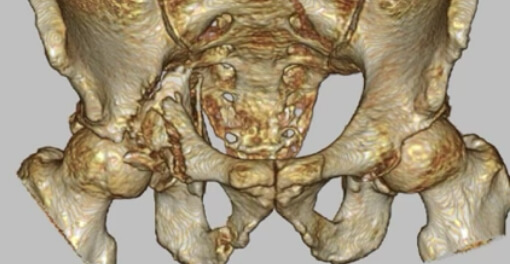

寛骨臼骨折症例

粉砕の強い右寛骨臼骨折の症例。前方・後方アプローチによる観血的整復固定術を行いました。